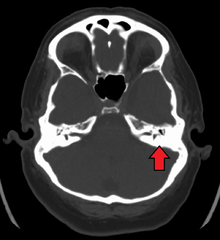

The diagnosis of mastoiditis is clinical—based on the medical history and physical examination. Imaging studies provide additional information; The standard method of diagnosis is via MRI scan although a CT scan is a common alternative as it gives a clearer and more useful image to see how close the damage may have gotten to the brain and facial nerves. Planar (2-D) X-rays are not as useful. If there is drainage, it is often sent for culture, although this will often be negative if the patient has begun taking antibiotics. Exploratory surgery is often used as a last resort method of diagnosis to see the mastoid and surrounding areas.[2][6]